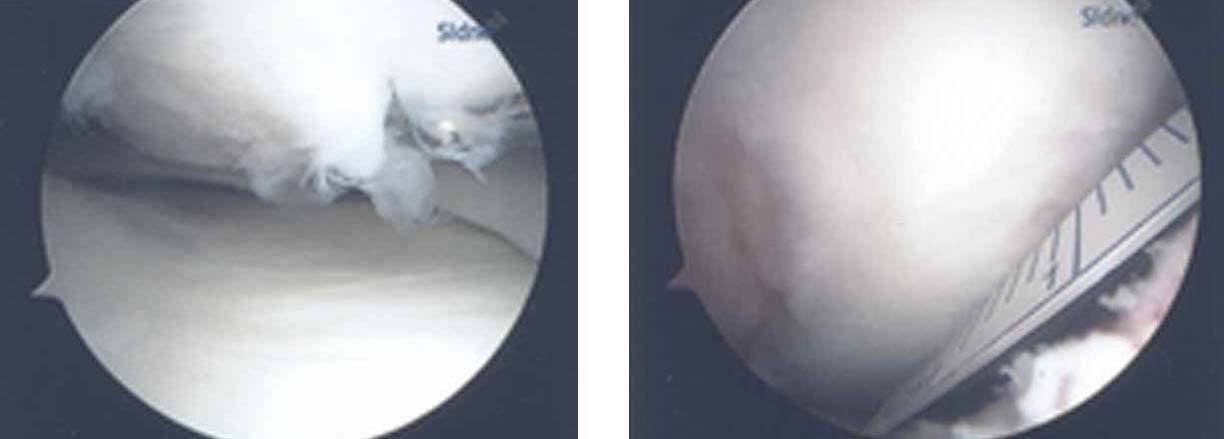

3.The arthroscopic views confirm a full thickness cartilage defect in the medial femoral condyle. The lesion is measured with a cut plastic ruler on the image on the right.